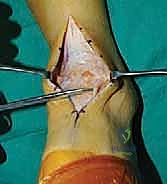

1. الوضعية والشق الجراحي (Positioning and Incision)

يستلقي المريض على ظهره (Supine position). يتم استخدام عاصبة (Tourniquet) حول الفخذ لتقليل النزيف وتوفير رؤية واضحة. يقوم الدكتور هطيف بإجراء شق طولي أمامي فوق مفصل الكاحل، عادة بين وتر العضلة الظنبوبية الأمامية (Tibialis Anterior) ووتر العضلة الباسطة الطويلة لإصبع القدم